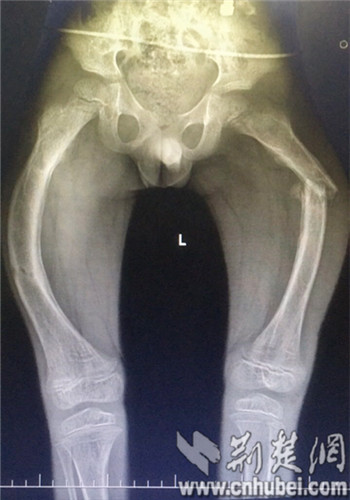

小峰骨折前腿部弯曲严重。 通讯员 胡南 提供

湖北日报(荆楚网)消息(记者白菲斐 通讯员 李丽)襄阳6岁半的“瓷娃娃”小峰(化名),6年来6次骨折,双侧股骨严重弯曲畸形,襄阳市中医医院开展的湖北首例可延长髓内钉手术,让小峰弯腿变直,恢复了正常身形。

经过四处打听,高先生带着小峰来到了襄阳市中医医院求诊,经过CT拍片显示:小峰的左侧股骨已弯曲成角130°,右侧达到90°。医院小儿骨科、麻醉科会诊后,结合患者病情及要求,决定为其行“切开复位截骨矫形可延长髓内钉内固定术”。这一手术在国内仅有少数几家大医院才能进行,为湖北省首例。